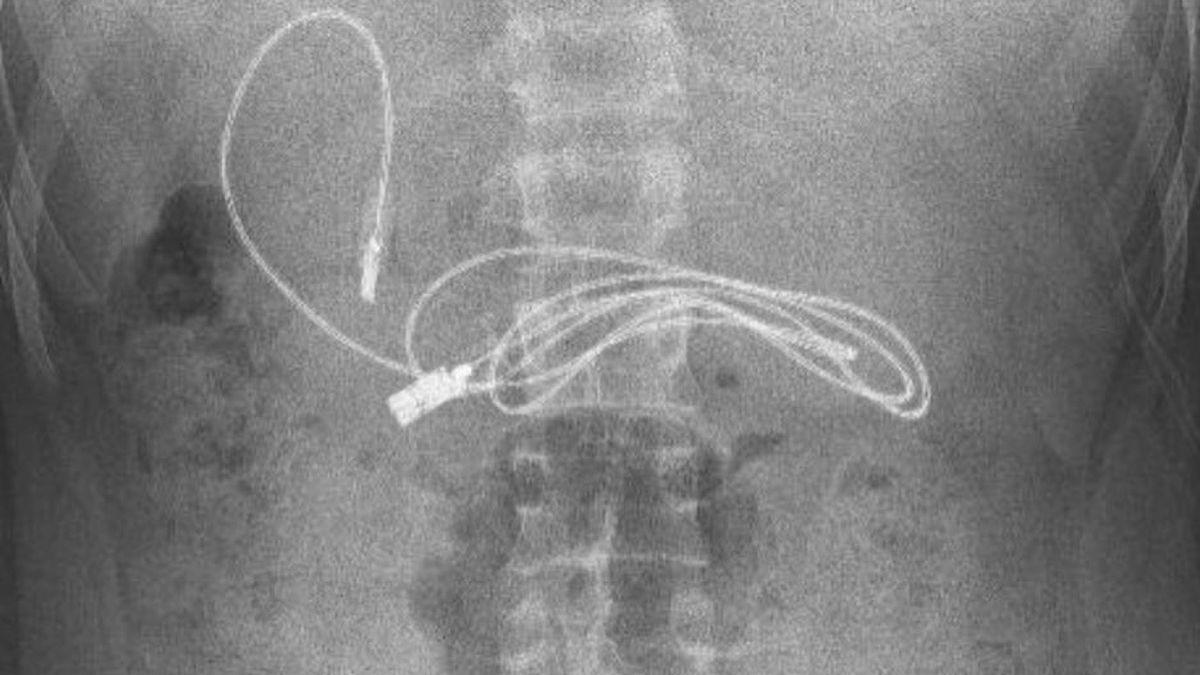

Selon le tabloïd anglais, l’adolescent, originaire de la ville de Diyarbakir en Turquie, a commencé à s’inquiéter après de violents maux de ventre et des nausées. Il s’est donc rendu à l’hôpital, où on lui a fait une radiographie pour comprendre l’origine du mal. Et là, grosse surprise pour les internes. Sur la radio, dans l'estomac, ils découvrent un câble de près d’un mètre de long qui convient à la recharge des téléphones ou des casques audios. Une chance : il n’est pas encore digéré. Pour faire face à cette situation assez insolite, le garçon est transféré à l’hôpital universitaire Firat d’Elazig, situé à environ trois heures de route de là, afin de voir un spécialiste, le gastro-entérologue pédiatrique Yasar Dogan.

Le Dr Dogan a procédé à une endoscopie pour retirer le câble de charge. Il s’agit d’une technique qui permet d’observer l'œsophage, l'estomac et le duodénum, grâce à un tube souple contenant une petite caméra afin d’effectuer des prélèvements et des gestes chirurgicaux. Il a déclaré aux médias locaux : "Nous avons évidemment eu du mal à retirer le câble, car une extrémité du câble était passée dans l'intestin grêle." En plus du câble, les médecins ont également du retirer un élastique à cheveux qui se trouvait aussi dans l'estomac de l'adolescent. Heureusement, cette aventure ubuesque finit bien : la procédure a été un succès et le jeune patient a pu être renvoyé chez lui en bonne santé.